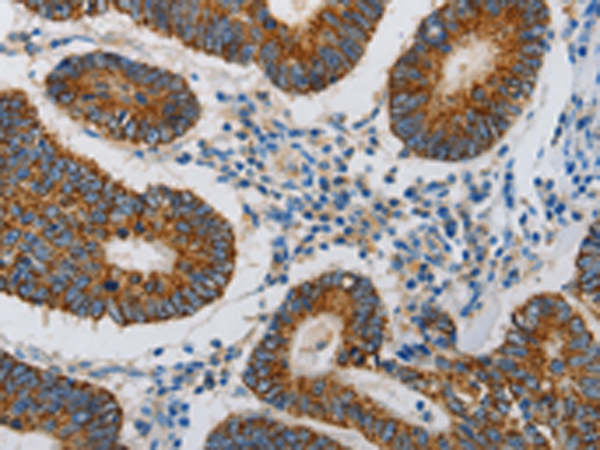

分类: 科研抗体货号: P10992别名: SCG10, SCGN10; SCLIP; RB3应用: WB,IHC反应种属: Human, Mouse